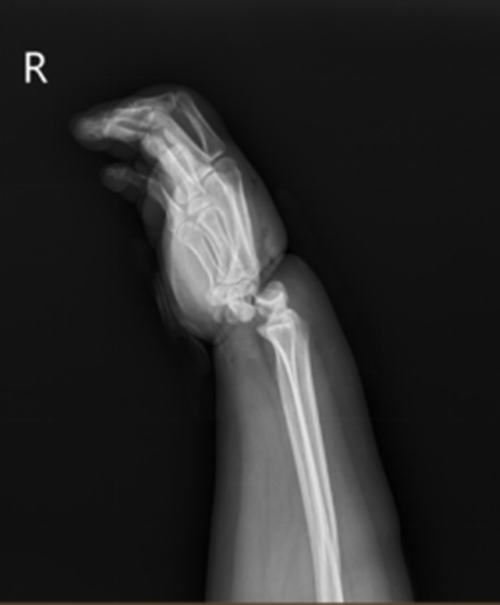

Khi Tiểu Mỹ được xe cấp cứu đưa đến Bệnh viện số 2 Ninh Ba, khớp cổ tay của cô đã bị gãy và trật hoàn toàn, bác sĩ xác định lưu thông máu kém. Sau khi tham khảo ý kiến của bác sĩ phẫu thuật vi phẫu tay, xác định rằng khớp cổ tay cũng như nguồn cung cấp máu động mạch và tĩnh mạch xa của Tiểu Mỹ có thể đã bị cắt đứt và cần phải ghép lại cổ tay bị đứt ngay lập tức.

| Tay phải của Tiểu Mỹ bị gãy, trật do cuốn dây thừng siết chặt vào cổ tay. |

"Lần đầu tiên tôi gặp bệnh nhân này, bàn tay phải của cô ấy sưng tấy rất nặng, cổ tay bị biến dạng nghiêm trọng, vùng da bị dây thừng siết cổ bị hoại tử và toàn bộ lòng bàn tay chuyển sang màu tím do thiếu máu cục bộ", bác sĩ cho biết sau khi khám.